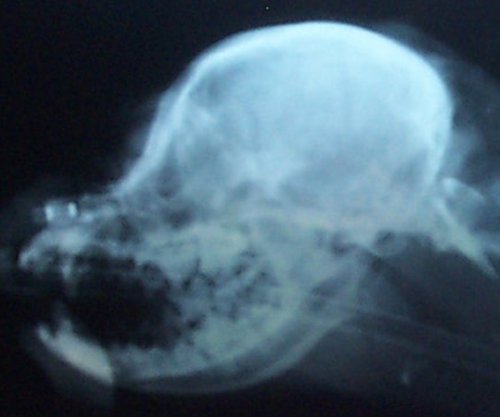

amount of CM. Here is a comparison of two skull x-rays which

show why this particular measurement indicates amount of CM. The

top one is a skull x-ray of a Cavalier with severe CM (and has

SM as well) and the bottom one is a skull x-ray of a Cavalier

with very little to no CM (and no SM).

The line was drawn from right in front of the 'hole'

(black spot), center of that curved bone (the 'jaw hinge' area)

to where the most thickened area of the skull ends (and the

occipital area begins). In the dog with almost no CM and no SM

you can CLEARLY see there is a lot more lower backskull left

behind/below that line as compared to the dog above--which

literally has almost none! This also happens to be the area

where the cerebellum sits so it would be common sense that the

dog in the top x-ray would have much less room for the

cerebellum than the dog on the bottom--and therefore more CM (chiari

malformation). There just isn't any skull left for there to be

enough room for the cerebellum. It appears here that a good

skull x-ray may be very useful in determining amount of CM and

therefore breeding towards a goal of less and less CM in future

offspring and thereby lessening the prevalence of SM. A skull

x-ray is much cheaper than an MRI which will enable many more

breeders to x-ray for amount of CM in the future as more

information becomes available.